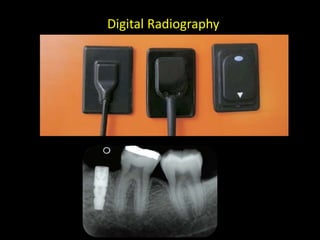

4. Digital radiography provides advantages like automated measurements and image manipulation but has higher initial costs and bulkier sensors.